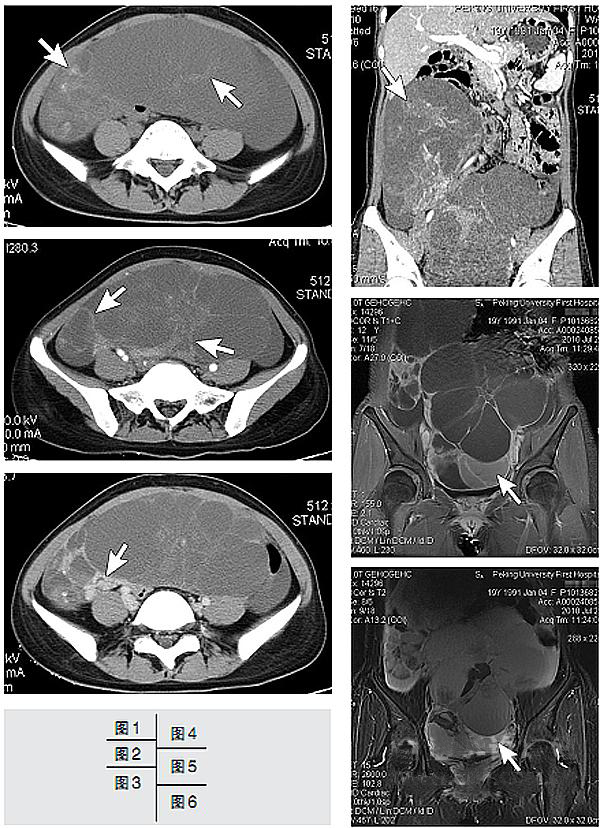

图1 CT平扫,为髂嵴上缘水平,可见下腹部有巨大囊性占位,囊内隐约可见分隔,部分有钙化(箭号)。

图2 增强CT扫描,较图1水平低,动脉期,示肿物呈多囊状,分隔轻度强化(箭号)。

图3 增强CT扫描,静脉期,病变的实性部分强化更加明显(箭号)。

图4 多层螺旋CT扫描,增强静脉期,冠状多平面重组(MPR)示病变为双侧、多房、囊实性,以囊性为主;右侧病变部位较高(箭号)。

图5和图6 磁共振成像(MRI),分别为脂肪抑制T1WI和脂肪抑制T2WI,冠状位,病变的多囊状结构显示更为清楚,多数囊内为T1较低信号和T2较高信号的液体,少数囊内T1WI与T2WI信号均较高,提示囊内液体的蛋白含量高或曾有过出血(箭号),盆腔内积液不明显。

病理检查示:卵巢(左侧)囊实性肿物,大小为23×14×8 cm,为中分化腺癌;肿瘤形态和免疫组织化学标记与横结肠癌一致,考虑为结肠癌转移。